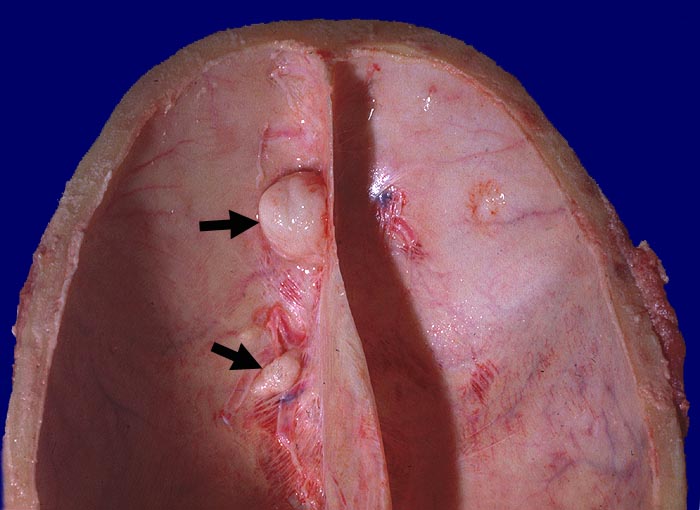

Die meisten Meningeome sind gutartig und fallen in die Kategorie WHO Grad I. Atypische Meningeome (WHO Grad II) machen zwischen 4.7-7.2% aller Fälle aus, anaplastische Menigeome (WHO Grad III) sind noch seltener. Meningeome sind oft multipel bei Patienten mit hereditärer Prädisposition und bei Neurofibromatose 2 sowie bei 10% der sporadischen Fälle. Meist wachsen Meningeome langsam. Sie sind in der Regel scharf begrenzt und sitzen der Dura breitbasig auf. Das Einwachsen von Meningeomgewebe in die Dura mater und/oder die benachbarte Schädelkalotte ist noch kein Malignitätszeichen und noch durchaus vereinbar mit einem benignen Meningeom WHO Grad I. Demgegenüber ist das Einwachsen in das benachbarte Hirnparenchym in aller Regel atypischen oder anaplastischen Meningeomen vorbehalten. Die Konsistenz ist prall-elastisch oder fest und das Tumorgewebe kann fokal verkalkt sein. Das Meningeom en plaque bedeckt flächenhaft die Dura als dünne Platte.

Der Dura breitbasig aufsitzender scharf begrenzter halbkugeliger Tumor.